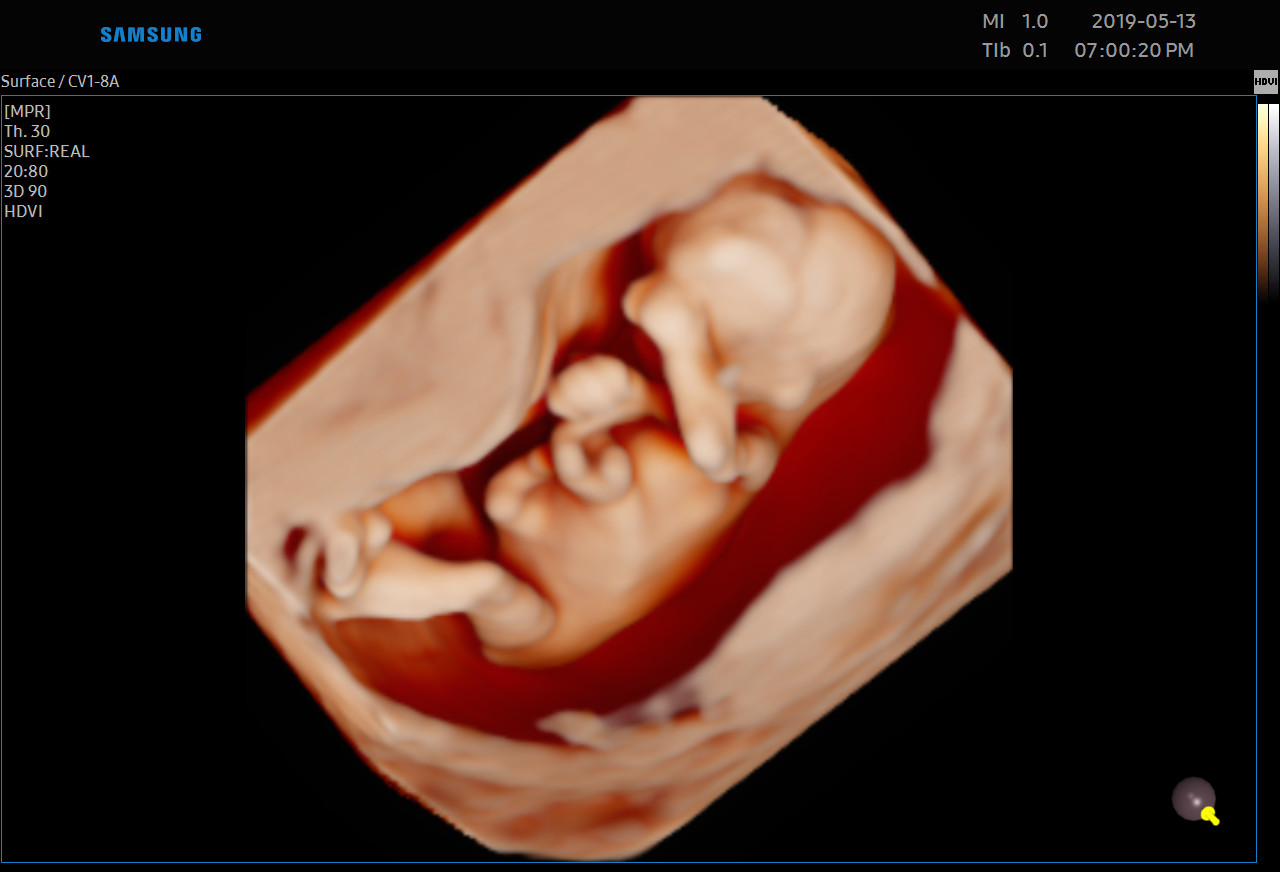

USG 3D dziecka w poradni ginekologicznej w Zambrowie –ocena NT, PAPP -A

Każdą kobietę w ciąży otaczamy kompleksową opieką, czuwając nad jej zdrowiem oraz prawidłowym rozwojem płodu. Podczas regularnych wizyt, zlecamy odpowiednie badania laboratoryjne. Korzystając z najnowszej generacji aparatu USG, przeprowadzamy bardzo dokładną diagnostykę obrazową – łącznie z USG 3D/4D płodu.

• Najnowsza generacja aparatu USG pozwala na przeprowadzanie dokładnej diagnostyki obrazowej, diagnostyki przepływów (Doppler).